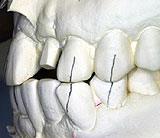

![]() ▲上顎前歯部でもほとんど1ピースで困らない歯軸で植立ができる |